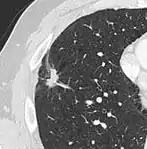

subpleural nodule.[9]

Round well-delineated solid lung nodule with smooth border.[9]